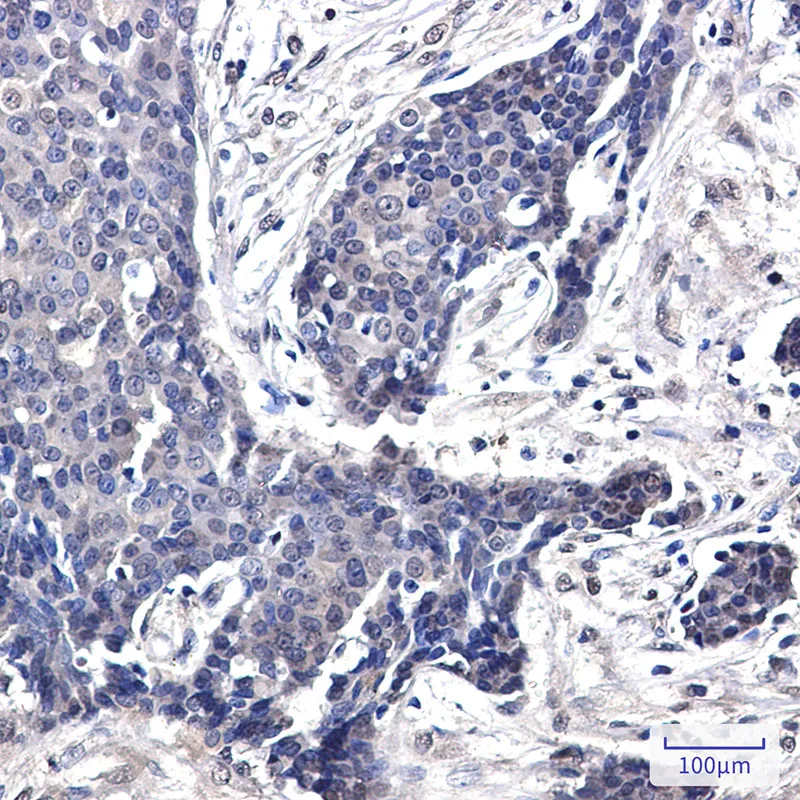

EGFR Rabbit Monoclonal Antibody

Cat: AMRe04076

Size1:50μL Price1:$158

Size2:100μL Price2:$288

Size3:500μL Price3:$1200

Application:WB,IHC-P,IP

Reactivity:Human

Conjugate:Unconjugated

Gene Name:EGFR

Size2:100μL Price2:$288

Size3:500μL Price3:$1200

Application:WB,IHC-P,IP

Reactivity:Human

Conjugate:Unconjugated

Gene Name:EGFR